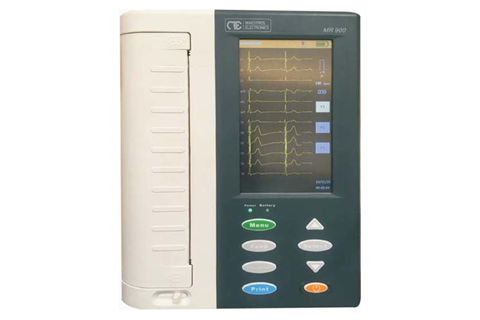

Bionet CardioTouch 3000 12 Channel ECG Machine

Bionet CardioTouch 3000 12 Channel ECG Machine

.jpeg) ECG 12 CHANNEL - MEDEXBIO

ECG 12 CHANNEL - MEDEXBIO

ECG MACHINE 6 CHANNEL - MEDEXBIO

ECG MACHINE 6 CHANNEL - MEDEXBIO

3 Channel ECG - MEDEXBIO

3 Channel ECG - MEDEXBIO

ECG MACHINE 12 CHANNNEL - INDIAN BRAND

ECG MACHINE 12 CHANNNEL - INDIAN BRAND

Digital 6 Channel ECG Machine

Digital 6 Channel ECG Machine

Burdick / Mortara ELI 250c EKG Machine (REFURB)

Burdick / Mortara ELI 250c EKG Machine (REFURB)

Pulsemed UK Cardiosense 12

Pulsemed UK Cardiosense 12

BPL ECG MACHINE 12 CHANNEL

BPL ECG MACHINE 12 CHANNEL

Zoncare 12 Channel ECG Machine

Zoncare 12 Channel ECG Machine

Edan ECG Machine SE-601 Series 6-Channel ECG

Edan ECG Machine SE-601 Series 6-Channel ECG

CONTEC ECG600G Digital 6 channel Electrocardiograph ECG machine EKG CE

CONTEC ECG600G Digital 6 channel Electrocardiograph ECG machine EKG CE

CONTEC ECG300G Electrocardiograph

CONTEC ECG300G Electrocardiograph

DAWEI 12Channel ECG Machine

DAWEI 12Channel ECG Machine

Dawei ECG Machine 3 Channel

Dawei ECG Machine 3 Channel

.jpeg) Comen – 12 Channel ECG Machine, CM1200

Comen – 12 Channel ECG Machine, CM1200

ECG 1200G – Contec

ECG 1200G – Contec

ECG 1212G – Contec

ECG 1212G – Contec

YKD MED ECG 3 CHANNEL

YKD MED ECG 3 CHANNEL

ECG 12 CHANNEL 3A CANADA

ECG 12 CHANNEL 3A CANADA

CardioCare 2000 ECG

CardioCare 2000 ECG

ECG Machine - 3 Channels

ECG Machine - 3 Channels